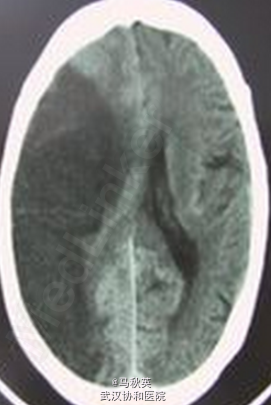

BP289/180mmHg,余生命征平稳,神志浅昏迷,查体合作,急性病容,心肺腹未见明显异常,双侧瞳孔等大等圆,对光反射减弱,左侧鼻唇沟变浅,颈强1指,四肢肌张力均增高,肌力检查不配合,右侧肢体偶见自发活动,左侧肢体疼痛刺激有反应,左侧巴氏征(+),右侧巴氏征可疑(+)。 B型脑尿钠肽106.4pg/ml,CK-MB12.6ng/ml,TNI289pg/ml,肌酸激酶1128U/L,乳酸脱氢酶330U/L,血钠150.3mmol/L 当地医院头颅CT示大面积脑梗。 入院后查颅脑CT:右侧额顶岛颞及部分枕叶见大片低密度影,其间散在高密度影,考虑大片脑梗塞并少许梗塞后出血。右侧脑肿胀,右侧脑室受压移位,中线左移越1.7cm,考虑大脑镰下疝 肺部CT:两下肺纹理稍粗乱,为少许炎症;两侧少量胸水,肝脂肪变,肝右叶钙化或结石,左叶小囊肿可能 出院前CT:右侧大脑半球大片状低密度灶,考虑为脑梗塞,较前密度减低、肿胀减轻,中线结构左移较前明显好转

诊断:1、大面积脑梗塞 2、脑疝形成 3、高血压病3级 极高危组 处理:告病危,持续心电监护、吸氧、加强脱水(静滴甘露醇,肌注速尿),利喜定静脉泵入,降血钠,动态监测患者心肌酶、BNP、心电图等变化,建议于脑外科行手术治疗,家属拒绝,要求保守治疗。